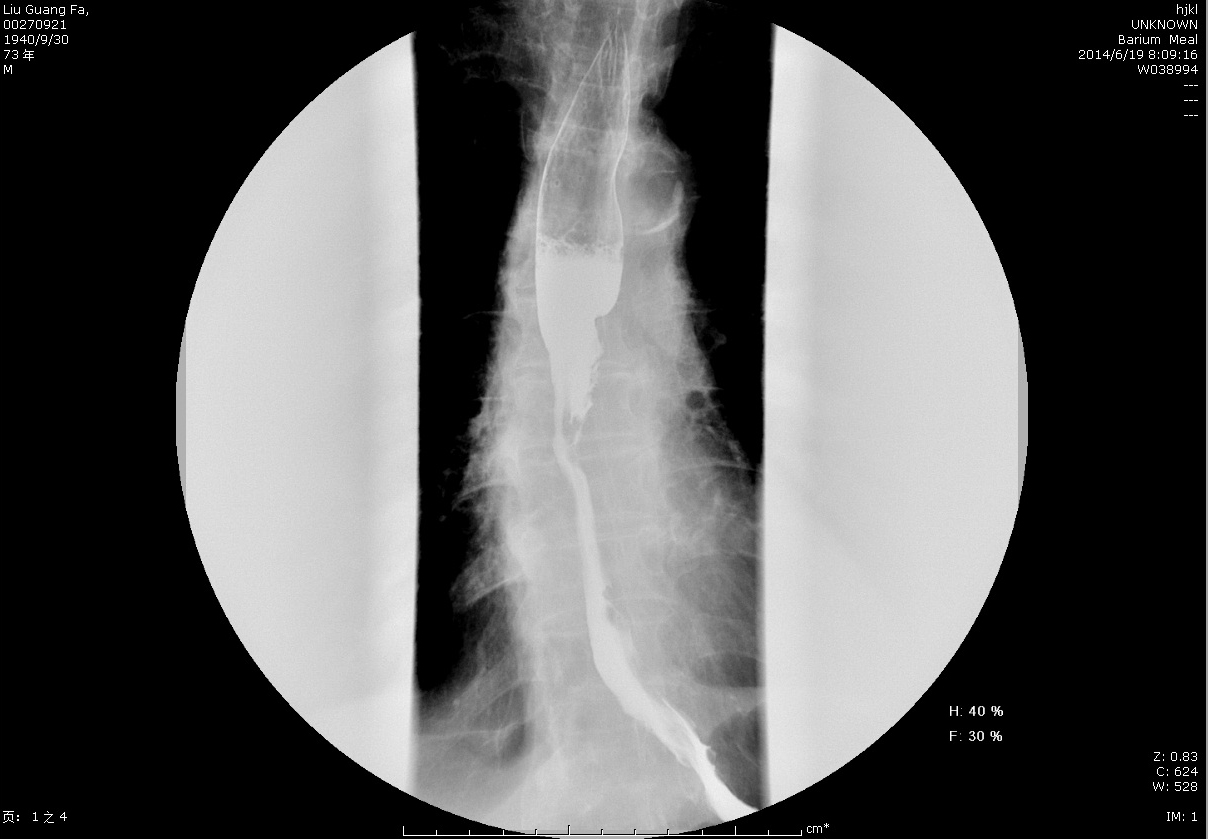

圖3+術前鋇餐